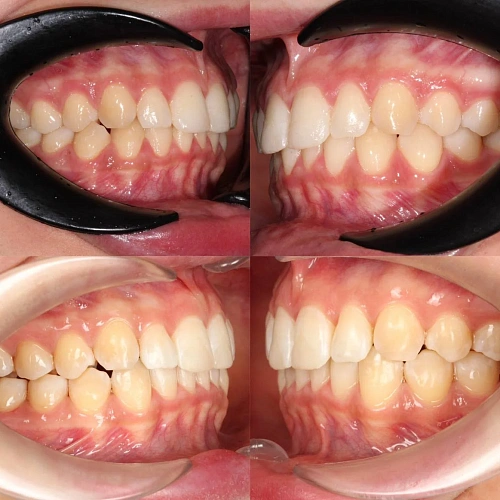

Обе челюсти сужены — зубам не хватало места, они стояли скученно на верхней и нижней челюсти. Нарушена кривая смыкания — жевательные зубы были на разной высоте.

Проблема: Пациентка живёт за рубежом и обратилась с жалобами на неровные зубы. При осмотре обнаружили сужение обеих челюстей, скученность на верхней и нижней, а также деформацию кривой смыкания — жевательные зубы стояли на разной высоте, из-за чего нагрузка при еде распределялась неравномерно. Дополнительная сложность — пациентка не могла приезжать на визиты часто.

Сложный случай: скученность на обеих челюстях плюс деформация кривой Шпее — жевательные зубы на разной высоте. Дополнительный вызов — пациентка живёт за рубежом, визиты реже, контроль сложнее. Три дозаказа — много, но каждый был обоснован: основной набор расширил дуги и убрал основную скученность, дозаказы последовательно довели смыкание до нормы. 82 капы за 30 месяцев — результат получен.